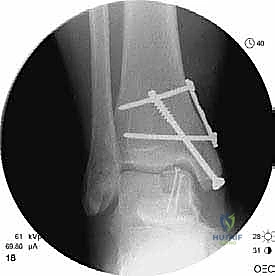

- التصوير المقطعي المحوسب (CT Scan): ضروري جداً للآفات الكبيرة. يوفر الـ CT صورة ثلاثية الأبعاد للعظم، مما يساعد الجراح في التخطيط الدقيق لعملية قطع العظم وحجم الطعم المطلوب زراعته.

الغوص العميق في جراحة الطعم الخيفي الهيكلي (Structural Allograft Reconstruction)

يهدف هذا الإجراء العبقري إلى استبدال الغضروف والعظم التالفين والميتين بنسيج سليم تماماً مأخوذ من متبرع متوفى (طعم خيفي - Allograft). هذا الطعم يتم تعقيمه وحفظه في بنوك الأنسجة العالمية وفقاً لأعلى المعايير الطبية الصارمة لضمان خلوه من أي أمراض معدية والحفاظ على حيوية الخلايا الغضروفية.

- الترميم التشريحي الحقيقي: يسمح باستعادة الشكل الهندسي الدقيق لعظم الكاحل، بما في ذلك المنحنيات المعقدة لكتف التالوس.